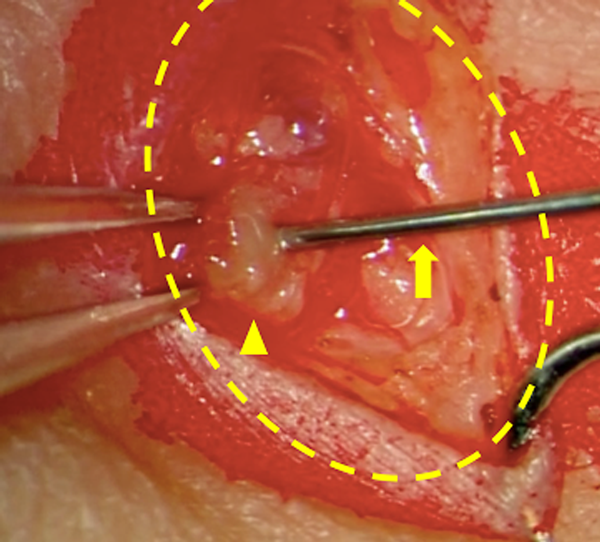

Fig. 5 Lymphatic venous anastomosis, intraoperative findings (Case #1)

Arrow head: Lymph vessel, Arrow: Branches of the Vein, Empty arrow: Main trunk of the Vein. Vein branches were enlarged with lymph fluid, result in clear expansion. In this case, three lymph vessels were anastomosed to three branches of the vein. Outer diameters were 1.0 mm for Main trunk of the vein, 0.6 mm, 0.35 mm for branch of the vein, and 0.2–0.3 mm for lymphatic vessels.

We prefer using LVA to establish lymph flow. This method was developed in Japan primarily for treating adult secondary lymphomas.22) It is a minimally invasive procedure, as the surgical fields are limited only on the superficial layers with small skin incisions; it is possible to perform this procedure under local anesthesia in adults.23) LVA is a relatively natural reconstruction method because the lymph flows into the veins eventually24) (Fig. 5). The underlying mechanism comprises releasing lymph from the lymph tract to the venous system; collecting lymph from the lower limbs into the central lymphatic system (e.g., pelvic lymph tract, chyle cistern, thoracic duct) into the veins, and/or collecting lymph fluid that has refluxed to the body surface from the central system, and/or small quantities of blood with hemostasis factors from the venous system that mix with the lymphatic tract to adhere to the leak site.25)